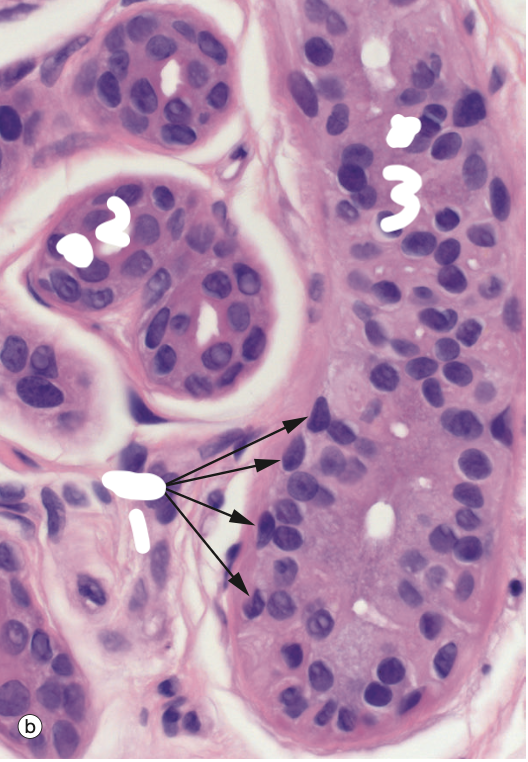

Identify the Structure

Apocrine Sweat Gland